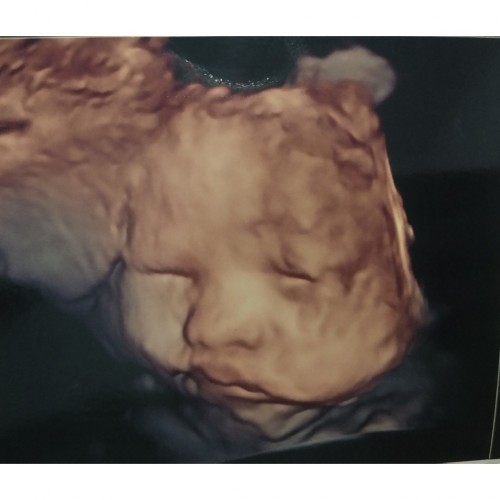

Bayiku suka malu2 klo di usg

32w, si dedek lgi cemberuut